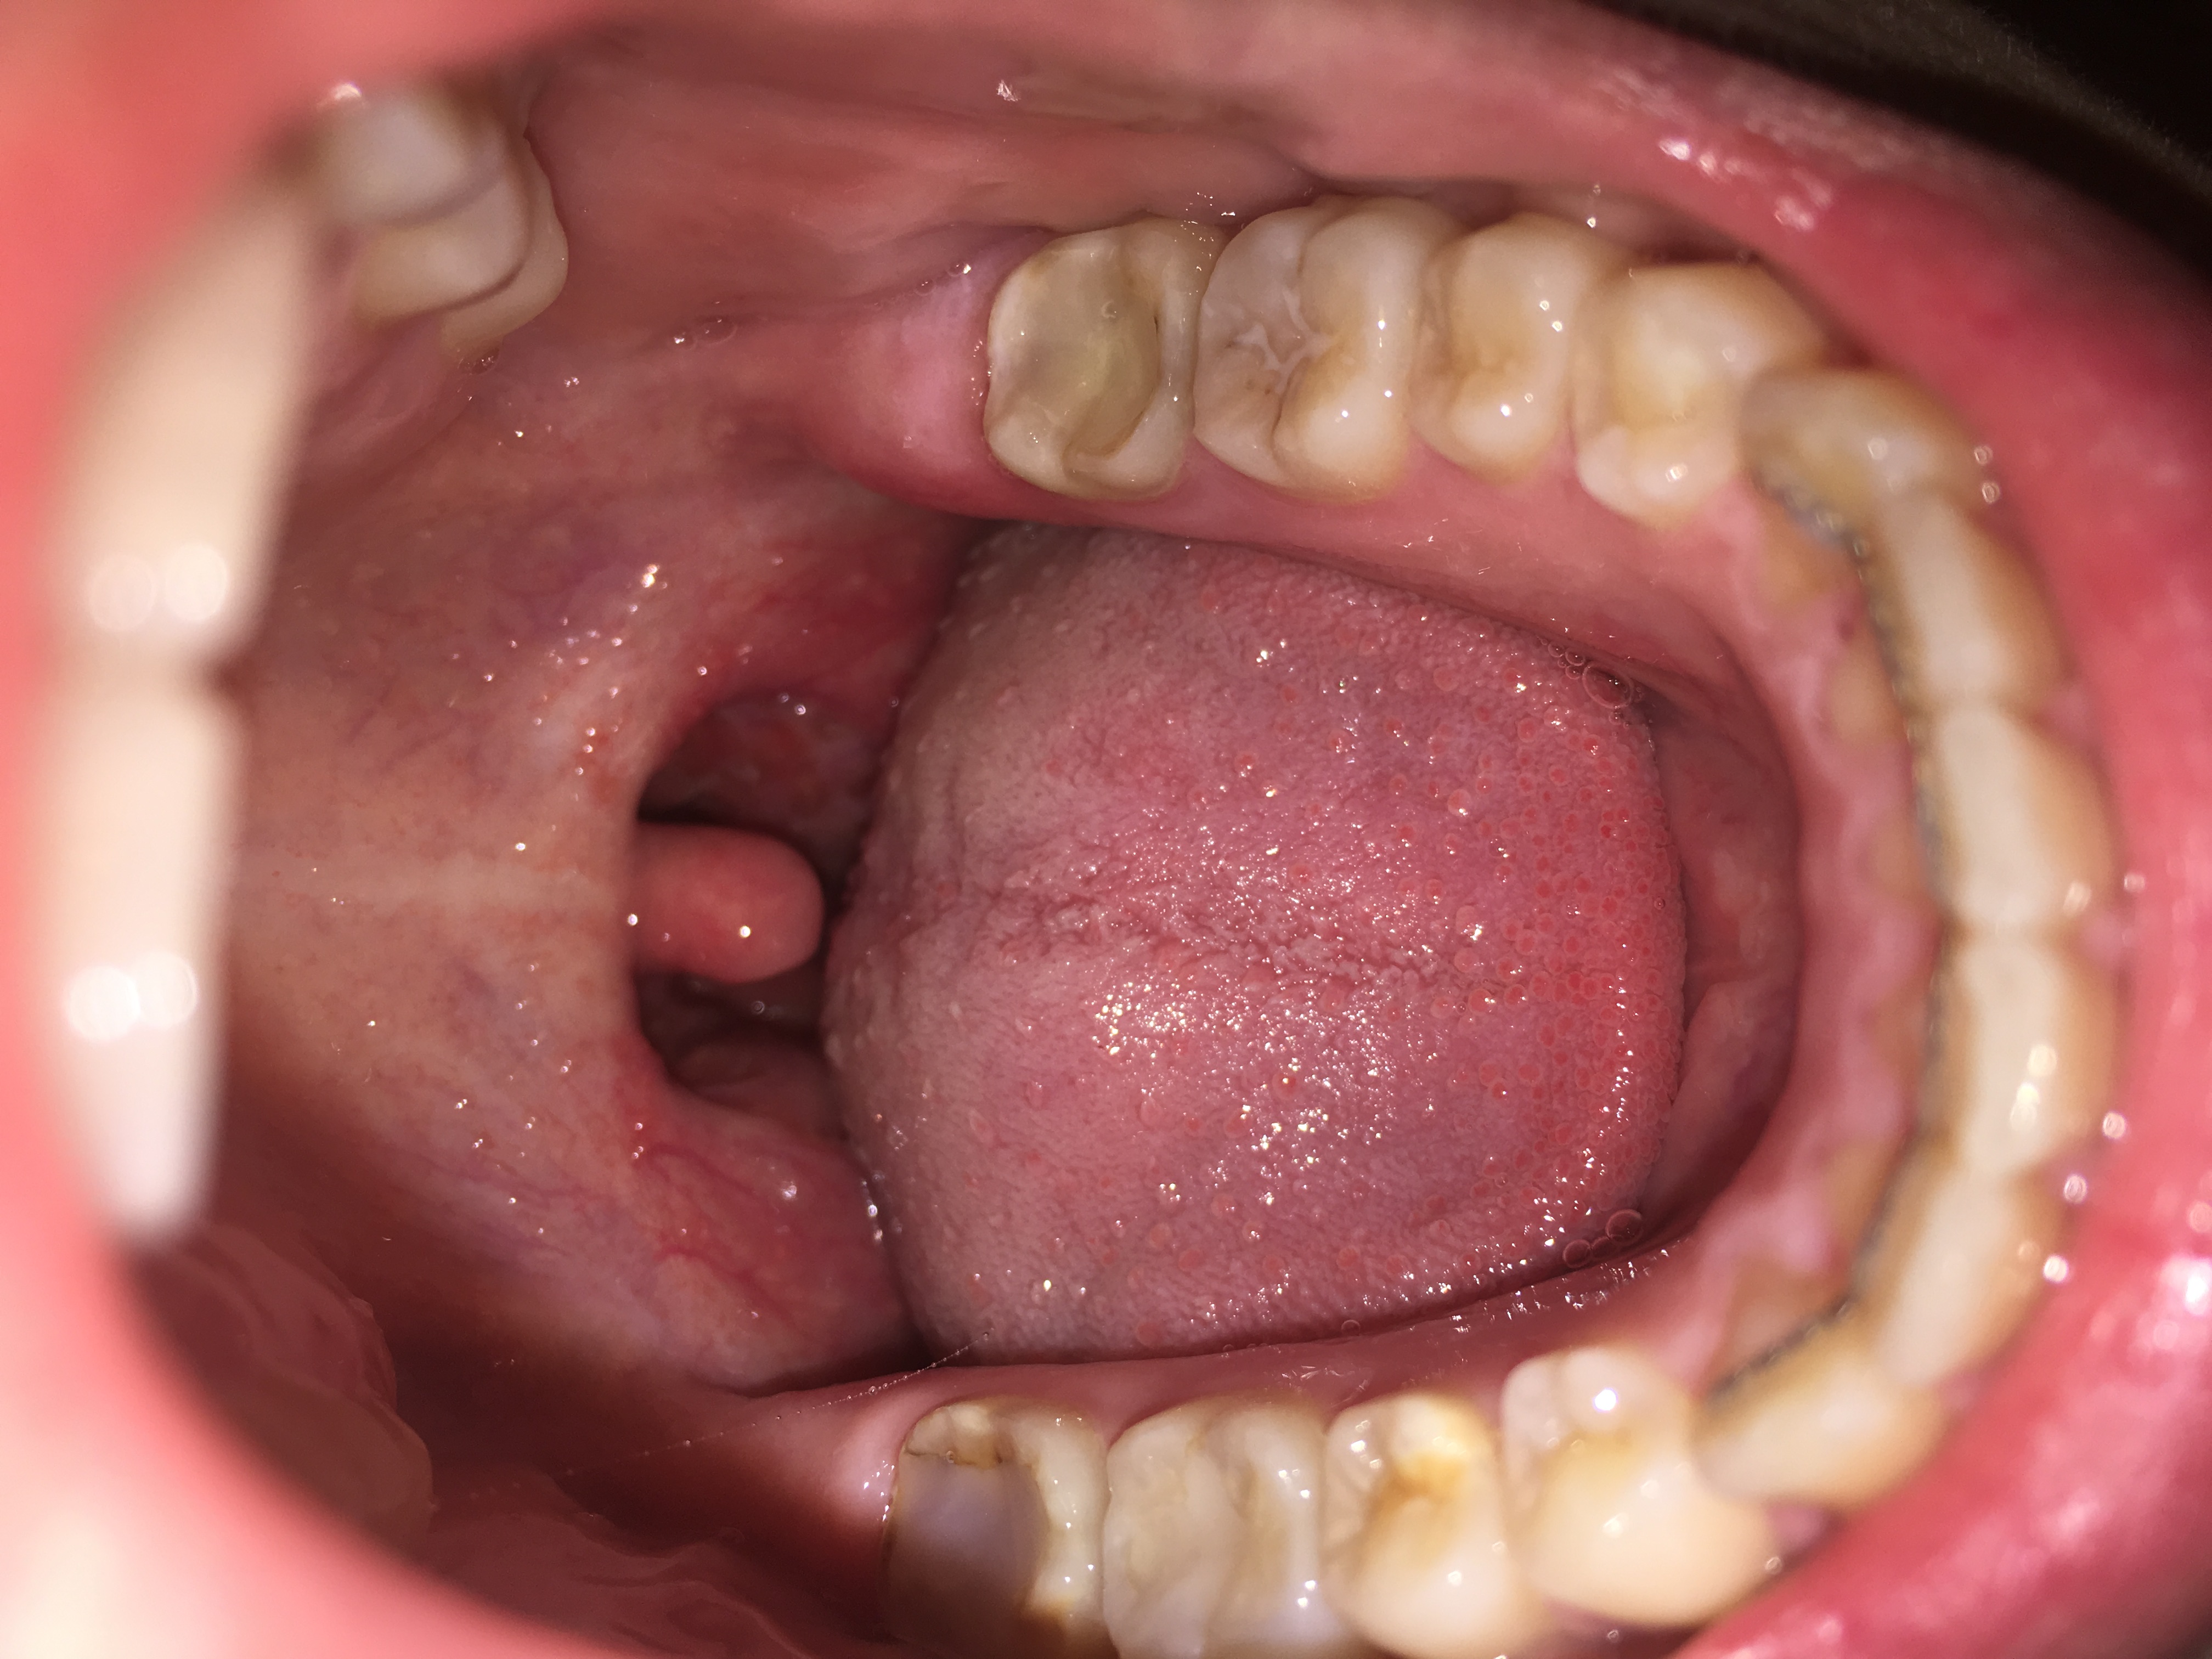

Eine Schwellung des Zahnfleisches ist ein Anzeichen für eine Entzündung. Hierbei wird Flüssigkeit im Gewebe eingelagert, welches durch eine Allergie oder Infektion hervorgerufen werden kann. Weitere Auslöser können sein: ein traumatischer Zahnunfall oder eine Verletzung. Ödeme. Blutungen. Fisteln am Zahnfleisch.. Auch eine Schwellung der betroffenen Areale (z. B. am Zahnfleisch, Gaumensegel, Gaumenzäpfchen, den Gaumenmandeln oder dem allgemeinen Oberkiefer) ist ein klassisches Entzündungszeichen. Begleitende Bläschen können auf einen Virenbefall oder Aphthen hindeuten. Gelbweiße Eiterherde weisen normalerweise auf eine Bakterienbesiedlung hin.

Was ist der geschwollene Bereich neben dem Gaumenzäpfchen? (Gesundheit und Medizin)

Merkwürdige Beule/ Schwellung am Zahnfleisch? (Gesundheit und Medizin, Gesundheit, Zähne)

Harter Knubbel rechtes oberes Zahnfleisch? (Gesundheit und Medizin)